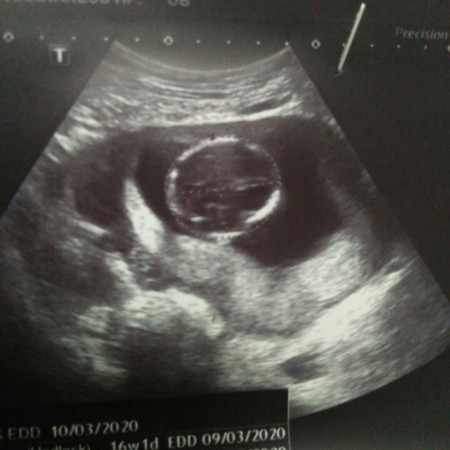

สอบถามเพศค่ะ อายุครรภ์16สัปดาห์

คุณหมออุลตราซาวด์แต่ไม่บอกเพศค่ะ อยากสอบถามคุณแม่ว่าเพศอะไรค่ะ

ถามหมอรึยังคะ? ถ้าดูเพศได้แล้ว ก็ไม่มีเหตุผลอะไรที่หมอจะไม่บอก ถ้าแม่ถาม ยกเว้นแต่ว่าอวัยวะยังไม่โตพอที่จะฟันธงเพศได้หรือเด็กหนีบขาไว้ ถ้าหมอยังบอกไม่ได้ ก็ไม่มีใครในนี้ให้คำตอบได้หรอกค่ะแม่ หมอรู้มากที่สุดแล้ว เขาเรียนมา แล้วภาพนี้ที่คุณแม่ลง ก็ดูเพศไม่ได้ด้วยจ้า มันไม่ใช่มุมที่ดูอวัยวะเพศจ้า